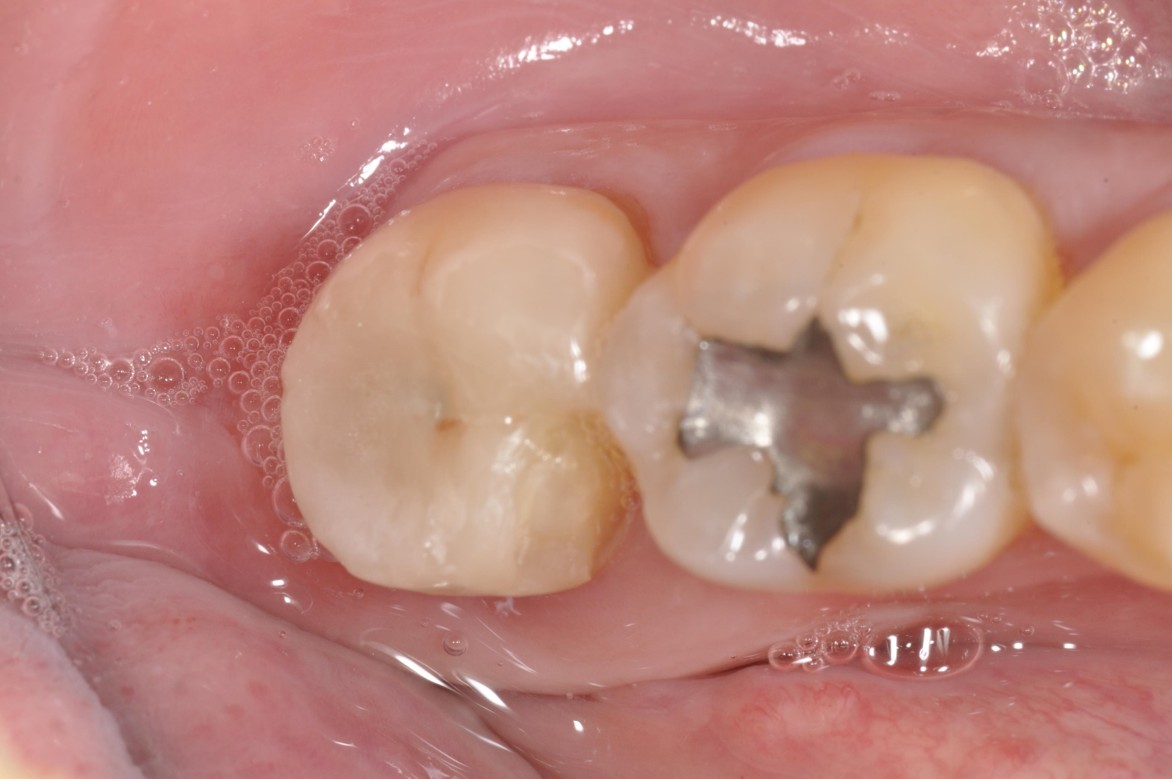

全鋯冠

治療後,咬合良好